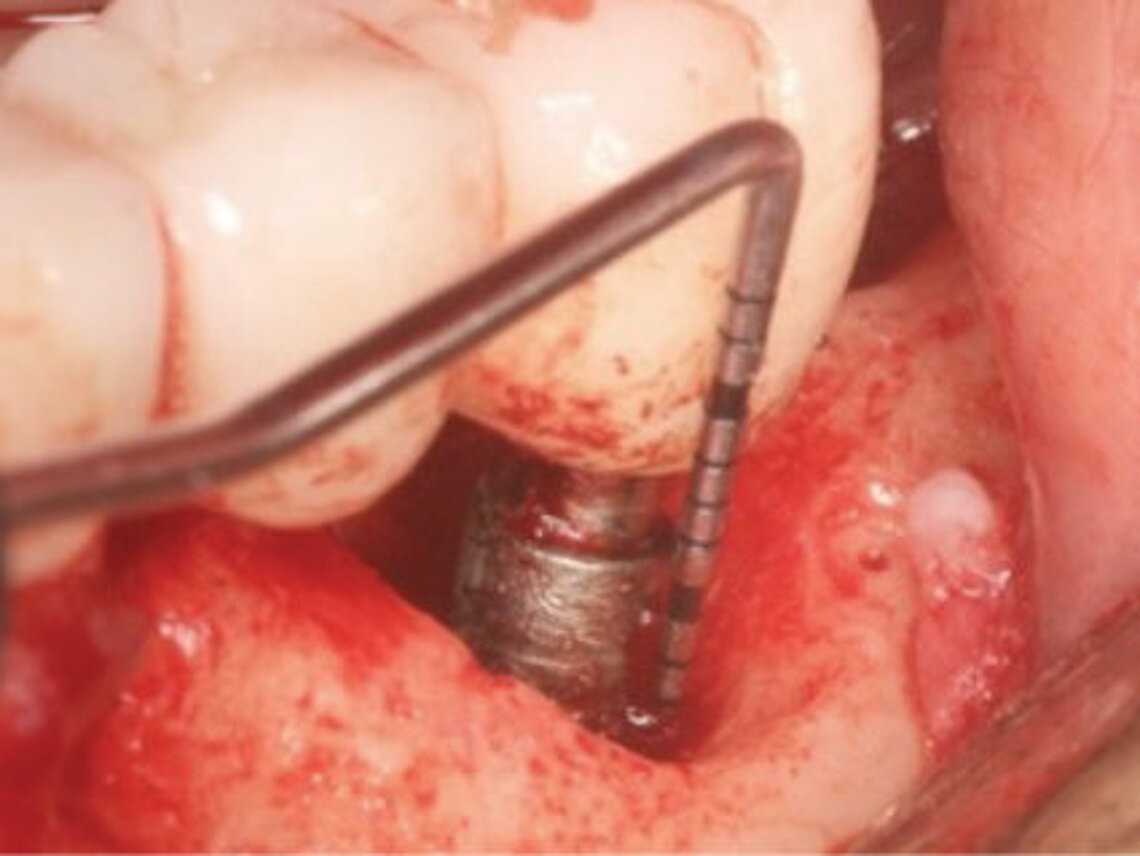

Peri-implant mucositis can be defined as an inflammatory lesion of the soft tissues (mucosa) surrounding the dental implant. Peri-implantitis is an inflammatory lesion of the mucosa affecting the supporting bone (crestal bone) with crestal bone loss and loss of osseointegration. Derks et al. report a prevalence of 43% for peri-implant mucositis and Jepsen et al. estimate that the prevalence of peri-implantitis could reach 22% (Figs. 1, 2).2,3 Peri-implantitis is usually accompanied by crestal bone loss (Fig. 3) and soft tissue changes in the peri-implant sulcus, which can be diagnosed by an increase in bleeding on probing (BOP) more than 5mm over previous examinations and/or suppuration8 (Fig. 4). Also excess of residual cement might contribute to crestal bone loss (Fig. 5).7

There are several conservative and surgical approaches available for the treatment of peri-implantitis. Non-surgical therapies are always the preferred treatment, while it is important to maintain implant cleanliness and oral hygiene. However, it is necessary to select approved oral hygiene instruments and to prevent surface damage with consequent generation of titanium particles and release of titanium ions.19-21 Surgical non-regenerative approaches include implant surface decontamination, degranulation of the defect, bone grafting and implantoplasty which can also lead to good clinical outcome.22 There is still ongoing research on methods for the decontamination of dental implants.23 The use of lasers was shown to be potentially beneficial in the treatment of peri-implantitis.24